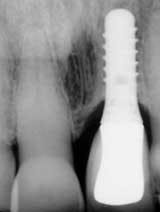

REVIEWING case photos and radiographs …

… communicates how far patients have come with implant TREATMENT.

Radiograph of 71-year-old woman before and after implant restoration

The case above is an excellent example in which someone who experiences continued periodontal breakdown around teeth despite treatment will fare better with implants and resist problems with future decay. Dr. Andrew Alpert of Aventura, Fla., placed the implants.